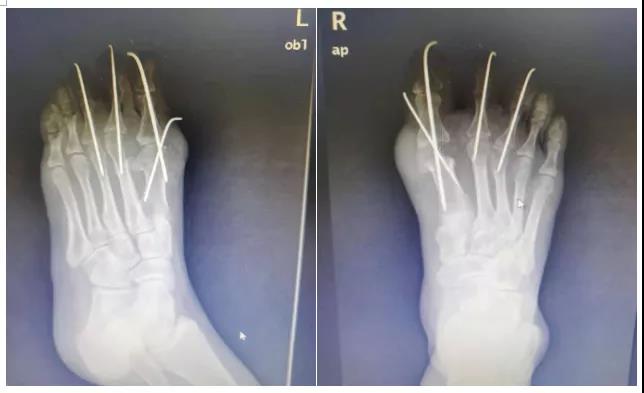

踇外翻截骨矫形

术后X片